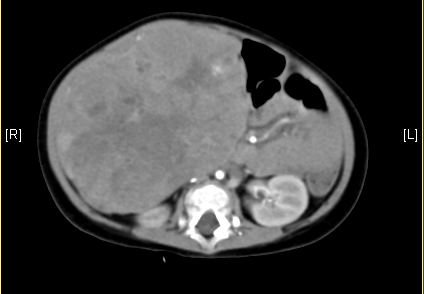

上腹部增强CT:考虑肝母细胞瘤可能性大。

静脉期